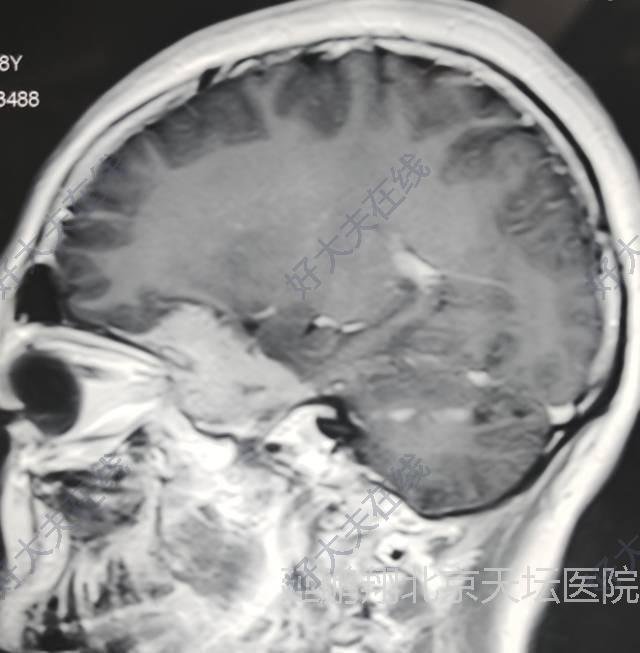

患者女性,38岁。间断性头痛3年左眼视力模糊1年。核磁显示左侧前床突脑膜瘤。

手术在全麻下进行,釆用左额颞入路,先切断肿瘤基底,阻断血供。肿瘤质地软,与脑组织粘连不紧,易分离,两者相隔有蛛网膜(图2),肿瘤切除后左侧嗅神经,视神经,颈内动脉,动眼神经均保护完好(图3)。

患者恢复顺利。复查核磁肿瘤消失。